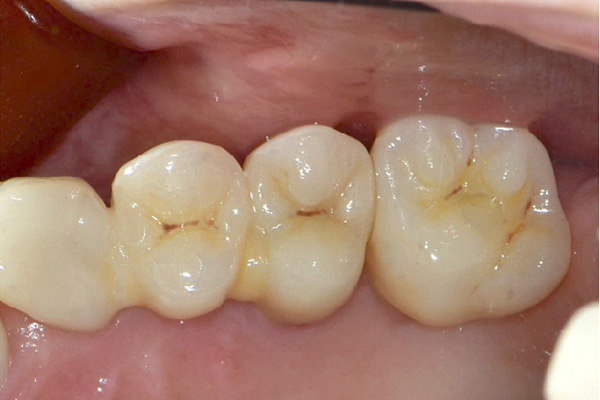

| 年代・性別 | 50代 男性 |

|---|---|

| 主訴 | 右下の歯がないのでインプラントをして欲しい |

| 治療期間 | 約6ヶ月 |

| 費用 | 600,000円 |

| 治療内容 | インプラント、骨造成、結合組織移植、セラミック修復 |

| 治療に伴うリスク | インプラント周囲炎 セラミックの破折、脱離 |